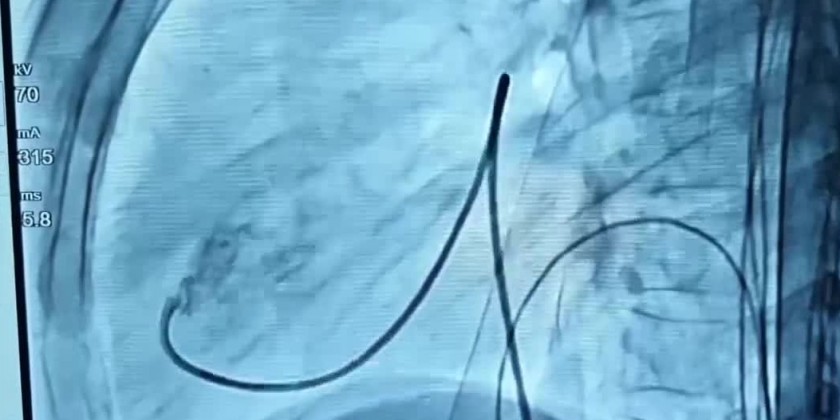

Myanmar and Vietnamese specialists conducted operations for patients with congenital heart disease using a device closure that is gently inserted in the groin to seal the hole without open-chest surgery at the Mandalay General Hospital on 23-24 September.

Prof Dr Kyaw Soe Win (Cardiologist) and Cardiologist Dr Nguyen Lan Hieu of Hanoi Medical University led the operations. The Myanmar and Vietnamese teams organized the workshop on Congenital Heart Disease Device Closure workshop and discussed the Echocardiogram for the treatments of Atrial Septal Defect (ASD), Ventricular Septal Defect (VSD) and Pulmonary Stenosis.

They successfully performed operations for 34 patients with congenital heart disease including two ASD patients, four VSD patients with Pulmonary Stenosis and seven PDA patients using device closure.